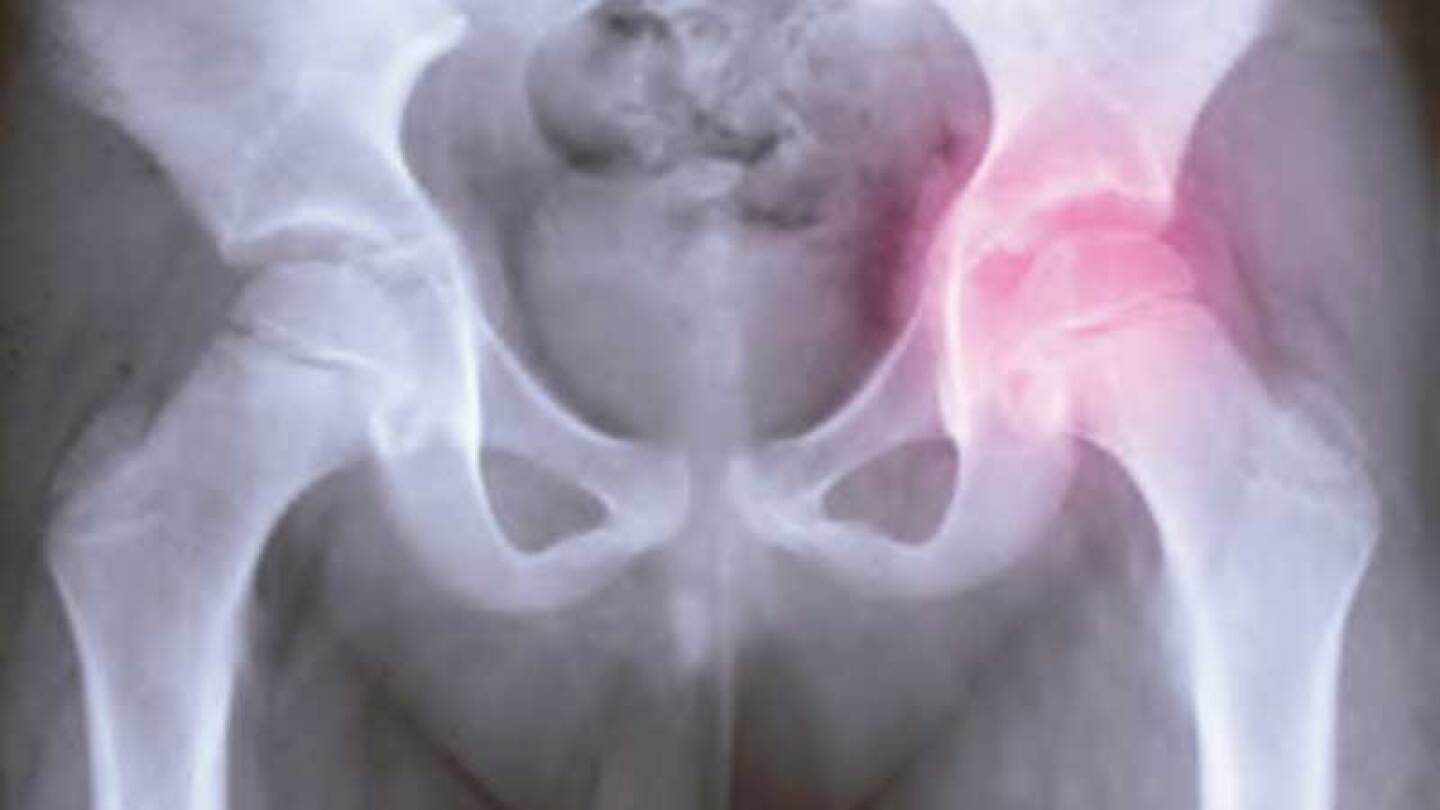

La coxartrosis es un padecimiento muy común; es un proceso degenerativo de articulación con un desgaste de cartílago, que es un amortiguador que protege los extremos de los huesos, tanto de la cabeza del fémur, como del acetábulo en la cadera. Se cierra el espacio que hay entre los huesos, haciendo que se dificulte el movimiento, se inflame y haya dolor. Se presenta en hombres y mujeres, y las principales causas son: disminución de la circulación en el hueso, lo que provoca que la cabeza del fémur se deforme. Puede ser por enfermedades o huesos maltratados, por luxaciones o fracturas; por displasia de cadera, trastornos del crecimiento, osteoporosis o desequilibrio de los miembros inferiores. Su incidencia depende de la actividad de las personas, por ejemplo, es común en corredores, taxistas, transportistas, y en general; en personas que tengan que estar moviendo con fuerza la articulación de la cadera; o por cuestiones como obesidad, embarazos múltiples y por la edad. El síntoma más importante es el dolor en la parte inguinal. El diagnóstico es con una exploración completa, rayos X, resonancias magnéticas, tomografías y exámenes de laboratorio, y según el tipo de artrosis, será el tratamiento.